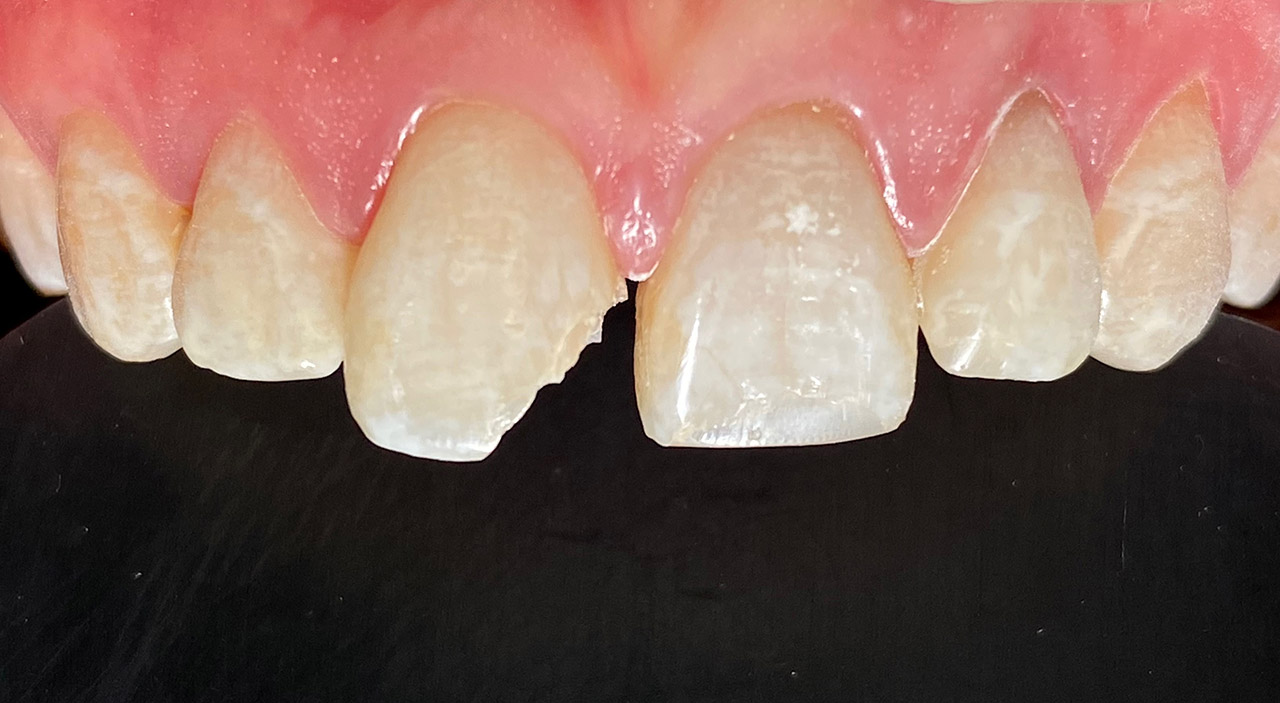

Internes und Externes Bleaching (Bleichen):

Nach Unfall mit E-Scooter unbefriedigendes Ergebnis der Erstversorgung (alio loco). Therapievorschlag: Stiftzähne?

Unsere minimalinvasive Therapie: Revision der Wurzelbehandlungen, danach internes und externes Bleaching, adhäsive Kunststoffüllungen in Schichttechnik. (Titel meiner Diplomarbeit 2003 “Die Vermeidung von Extraktion und Wurzelspitzenresektion durch zeitgemässe Endodontie in der Privatpraxis”)